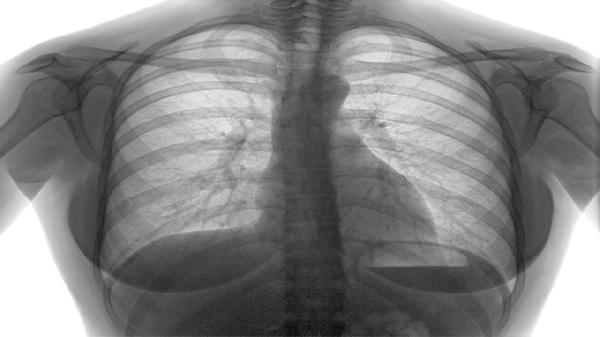

5、肺脓肿患者需定期复查,包括胸部X光或CT检查,以评估治疗效果和病情进展。若出现持续发热、咳血或呼吸困难等症状,应及时就医,排除其他潜在疾病,如肺癌或结核。